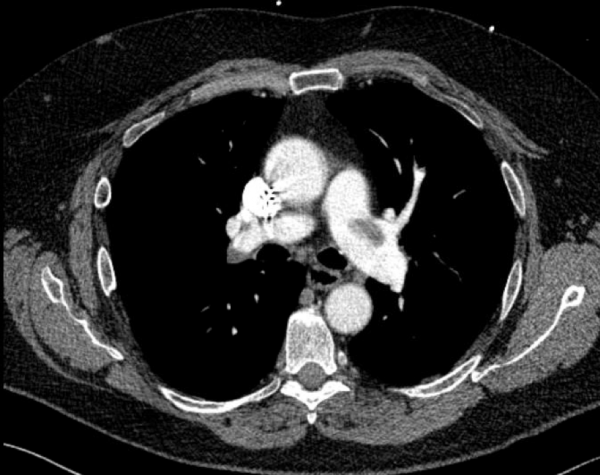

CT angiography of the chest with intravenous contrast was performed.

There is a filling defect straddling the bifurcation of the pulmonary trunk extending into the distal branches of the right lower, right middle, right upper and left upper lobe consistent with a saddle embolism. Bedside echocardiography revealed mild concentric hypertrophy, an ejection fraction of 60%, with normal right ventricular global systolic function, with no evidence for an elevated right ventricular systolic pressure.